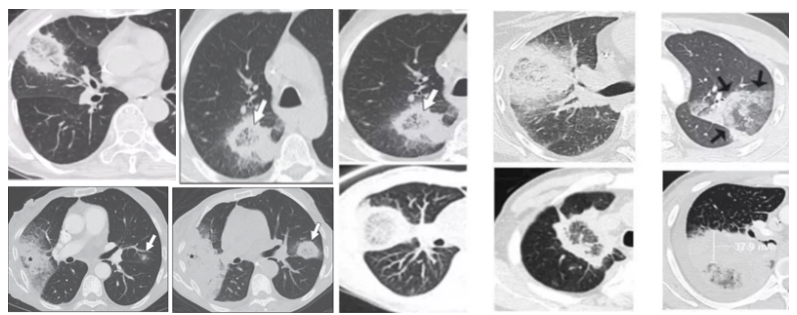

相关文献报道很少,涉及8例流感病毒相关毛霉病(IAM)和7例新型冠状病毒相关毛霉病(CAM)。笔者总结了这些患者的临床特点:①平均年龄为55岁,所以IAM/CAM可能与高龄无关;②男性发病居多,占73.3%,其中IAM发病率为62.5%,CAM发病率为85.7%;③存在至少一种除病毒感染外的基础病;④严重程度(重度);⑤危险因素:糖皮质激素,粒缺,高血糖;⑥毛霉病类型:IAM(肺毛霉病),CAM(鼻-眶-脑型毛霉病);⑦毛霉病诊断距病毒性肺炎时间:平均16.3天,偏晚。IAM/CAM的影像学相对特异,包括反晕征、厚壁空洞、大片实变伴支气管截断征(毛霉多导致支气管截断、破坏,曲霉多为支气管壁增厚、狭窄)等(图8,图9)。此外,增强CT/CT肺动脉造影(CTPA)对于毛霉病的诊断也非常重要,尤其是诊断假性动脉瘤—真菌性血管瘤,以及发现血管受侵(毛霉多侵犯大中血管)(图10,图11)。在上述15例患者IAM/CAM患者中,手术比例达到50%,大多采用了单药或联合抗真菌治疗,但病死率仍然高达66.7%,IAM病死率为37.5%,CAM患者病死率甚至达到100%。(1)危险因素:高龄可能并非病毒合并毛霉病的高危因素(平均55.7岁);男性发病更常见(73.3%);糖尿病、酸中毒、糖皮质激素是其危险因素。